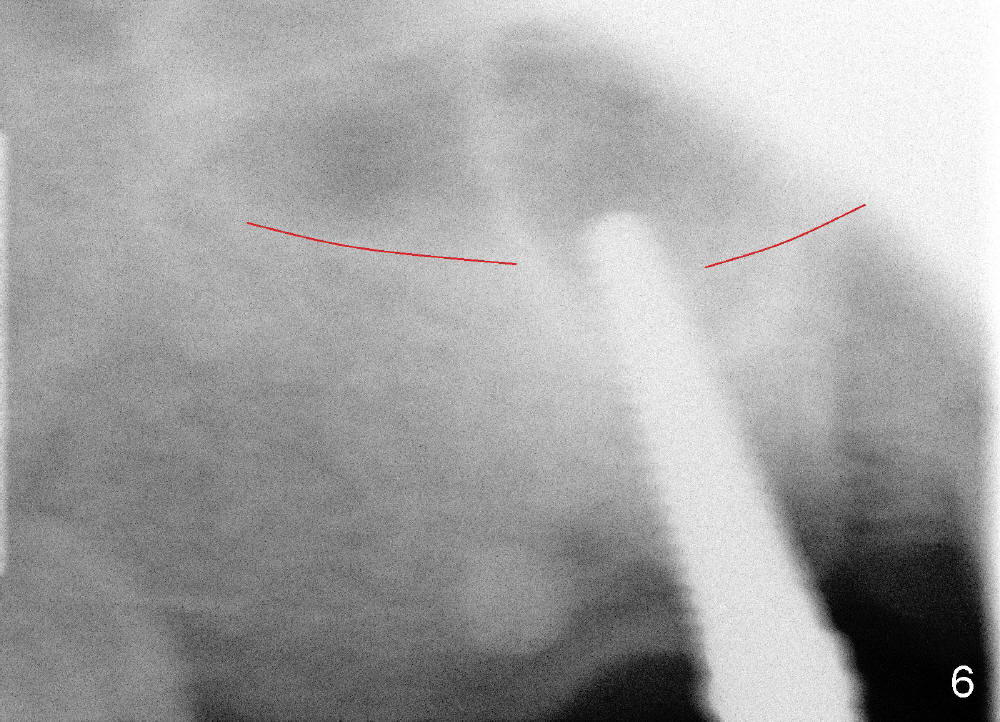

Osteotomy can be done in the palatal socket or the septum in this case to avoid implant thread exposure. Initial osteotomy is created in the palatal socket by using series of tap drills (4.5,5,6,7x17 mm) without stability or enough length (Fig.5; red line: sinus floor). The second osteotomy is made in the septum by using series of tapered osteotomes (2,3,4x17 mm), followed by 4.5x20 mm tap at depth of 17 mm with satisfactory binding (Fig.6). To avoid further sinus penetration and close the socket as much as possible, 5 and 6x17 mm taps are used at 14 mm deep (Fig.7). Nasal blowing reveals air leaking after the last tap. A 6x14 mm tapered implant is placed with insertion torque >60 Ncm (Fig.8). No bone graft is placed. The implant is surrounded by gingiva proximally and lingually and coagulation buccally. The wound is covered by perio dressing.